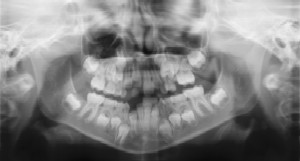

Dental Radiographs (X-Rays)

Radiographs (X-Rays) are a vital and necessary part of your child’s dental diagnostic process. Without them, certain dental conditions can and will be missed.

Radiographs detect much more than cavities. For example, radiographs may be needed to survey erupting teeth, diagnose bone diseases, evaluate the results of an injury, or plan orthodontic treatment. Radiographs allow dentists to diagnose and treat health conditions that cannot be detected during a clinical examination. If dental problems are found and treated early, dental care is more comfortable for your child and more affordable for you.

The American Academy of Pediatric Dentistry recommends radiographs and examinations every six months for children with a high risk of tooth decay. On average, most children's dentists request radiographs approximately once a year. Approximately every 3 years, it is a good idea to obtain a complete set of radiographs, either a panoramic and bitewings or periapicals and bitewings.

Children's dentists are particularly careful to minimize the exposure of their patients to radiation. With contemporary safeguards, the amount of radiation received in a dental X-ray examination is extremely small. The risk is negligible. In fact, the dental radiographs represent a far smaller risk than an undetected and untreated dental problem. Lead body aprons and shields will protect your child. Today’s equipment filters out unnecessary x-rays and restricts the x-ray beam to the area of interest. High-speed film and proper shielding assure that your child receives a minimal amount of radiation exposure.